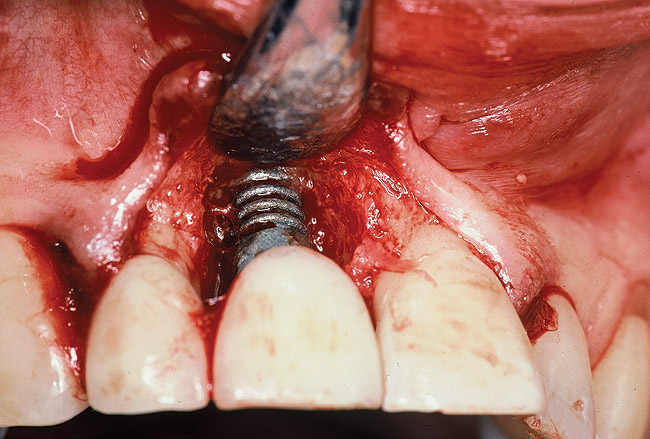

A 46-year-old man with an unremarkable medical history was referred for evaluation and treatment of the maxillary right central incisor implant. The implant, which had been placed 6 years prior, had never caused any problems until recently, when the patient noted both swelling and soreness at the site. Following 10 days of amoxicillin 500 mg tid, purulence was still present upon palpation of the tissue, and the patient was referred for consultation (Figure 6). Probing attachment loss of 10 mm on the distal aspect and 5 mm on the mesial were measured around the implant. Bone loss was advanced on the periapical radiograph at both the mesial and distal aspects of the hydroxyapatite-coated implant (Figure 7). Full-thickness facial and lingual flaps were reflected to access the implant and surrounding bone, with care taken to preserve the papilla. The defects around the implant on the mesial and distal were 1-wall, and bone loss was present on the direct facial and palatal aspects as well (Figure 8). The surface of the implant was decontaminated, followed by application of enamel matrix derivative. The lesion was filled with freeze-dried bone allograft (Figure 9). The graft-biologic was covered by a flowable polymer barrier (Figure 10). The flaps were coronally advanced and secured with monofilament sutures (Figure 11). The patient was prescribed amoxicillin with clavulanic acid and an oral rinse of 0.12% chlorhexidine during the post-operative period. The healing progressed uneventfully, achieving both a favorable soft-tissue profile and substantial bone fill, as determined radiographically. These results were stable for 7 years (Figure 12 and Figure 13).

Figure 11  The flap was sutured.

Figure 11